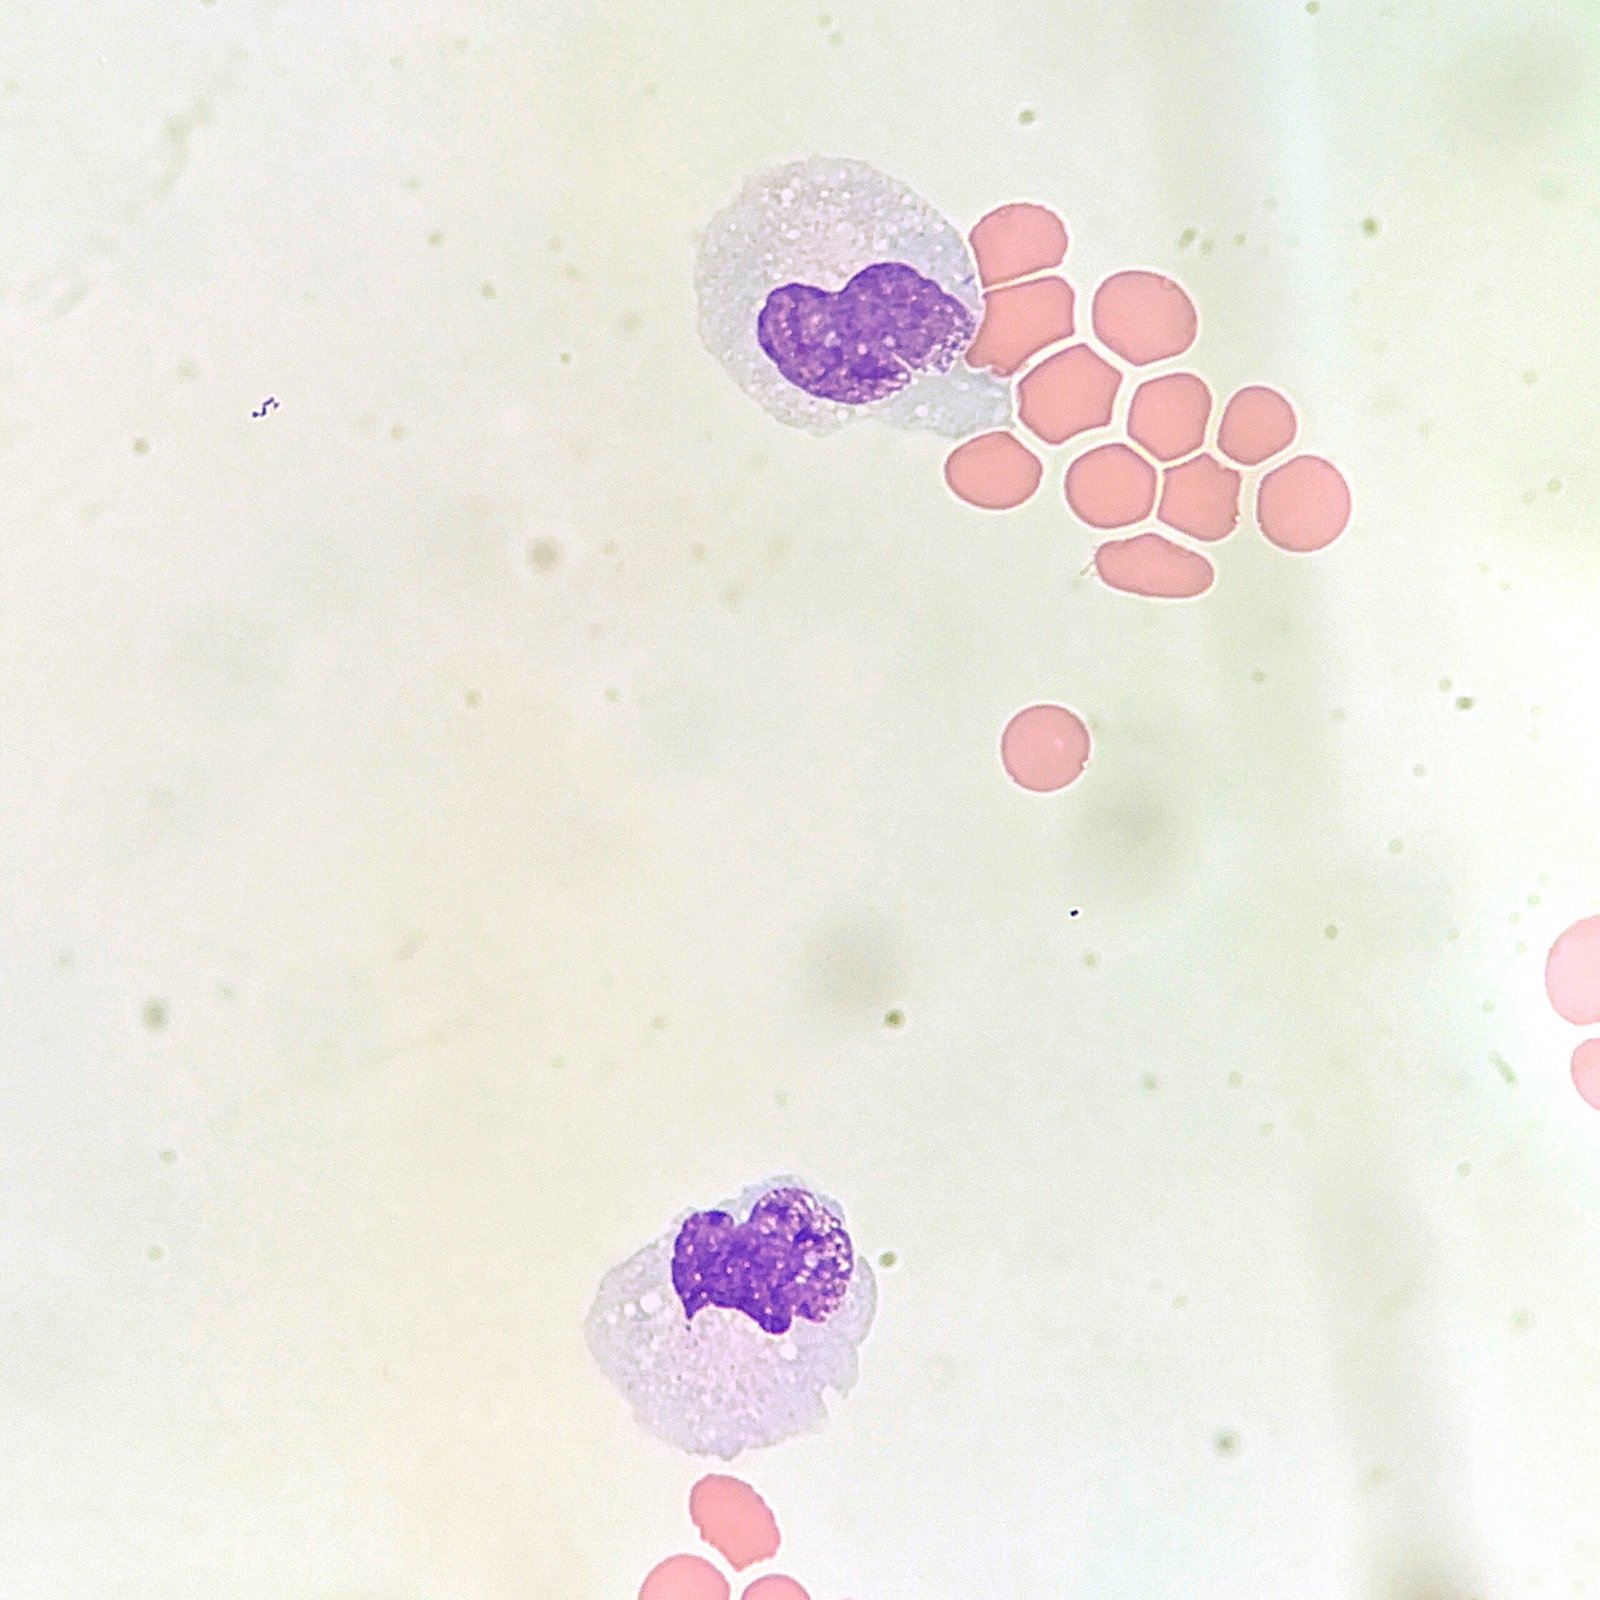

Mesothelial cells are described as having a “fried egg” appearance. They have a round to oval nucleus with smooth borders and evenly distributed chromatin. Nucleloli are usually present. Mesothelial cells may also be multinucleated.

Macrophages are about the same size as mesothelial cells, so the two can often be confused. Macrophages can usually be differentiated by the presence of vacuoles and a lacey chromatin. If both cell types are present and differentiation is difficult, take a look around the slide to get an idea of each kind of morphology before starting a differential.